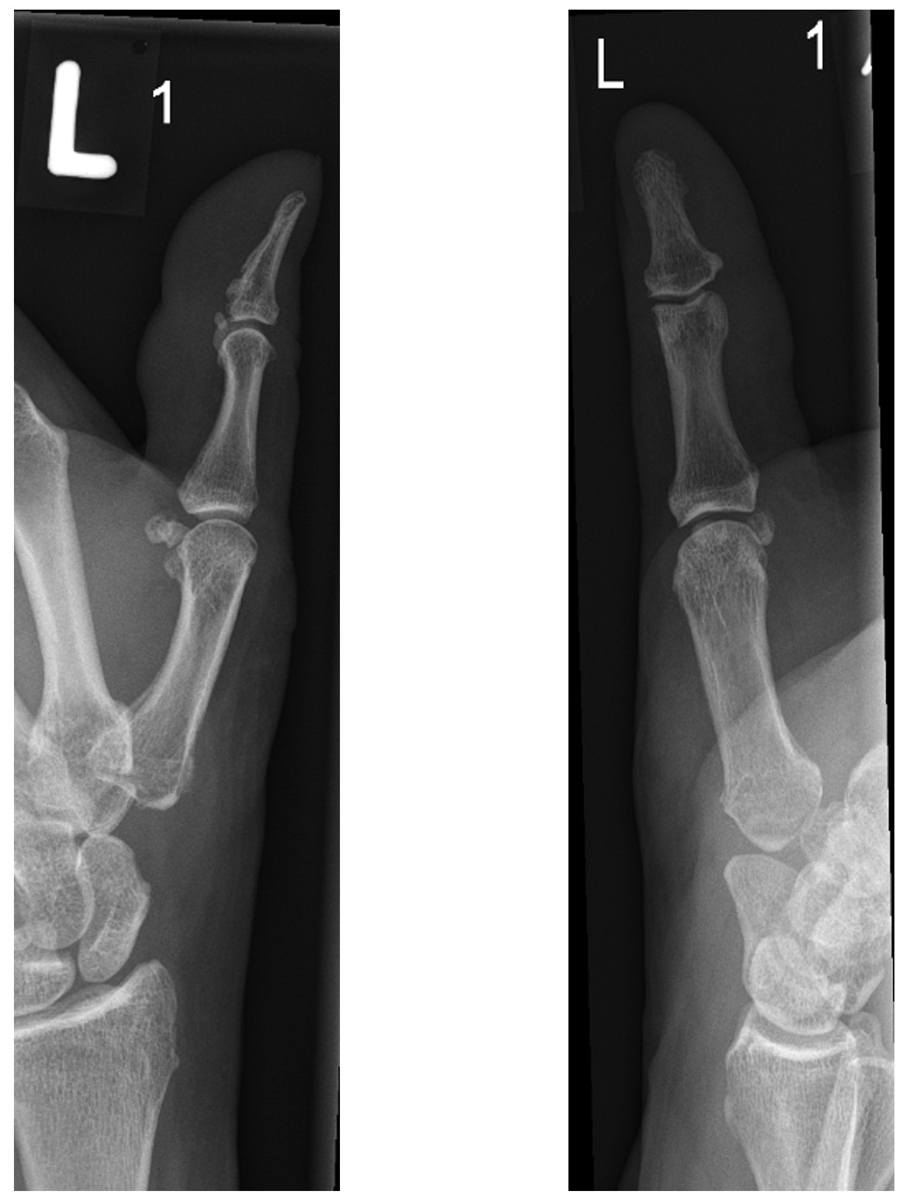

The latter adds suspension with a tendon strip in order to support the first metacarpal bone, as well as filling the trapezial space with the partially resected local tendon (fig. 4) [47]. Both interventions show equal long-term outcomes, nevertheless simple trapeziectomy is a shorter procedure with slightly lower complication rates [48–51]. Nevertheless, most hand surgeons prefer LRTI to simple trapeziectomy [52] and it thus represents the most common surgical therapy for patients suffering from advanced stages of TMO [6]. A possible explanation could be that the ligament reconstruction allows initial suspension and early functional rehabilitation. Ligament reconstruction and interposition using artificial material or allografts have fallen out of favour due to significantly higher complication rates [53].

Figure 4 Left thumb after trapeziectomy with ligament reconstruction and tendon interposition. Lateral view (left) and anterior-posterior view (right). After complete resection of the trapezial bone, the height of the thumb is preserved by filling the trapezial space with the partially resected flexor carpi radialis tendon. This resection-tendon-interposition and suspension arthroplasty is used by many hand surgeons.